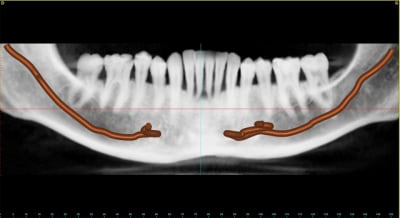

Voilà les images d'un cas de MCI partiel qui je l'espère sera réalisé avant. Cela concerne de 32 à 42 et la 15.

Ce sera j'en sur l’intérêt d'un débat. La question est: Comment faire une extraction implantation immédiate sure reproductible et prévisible; dans une même séance. Évidemment il y aura en même temps un aménagement tissulaire esthétique.